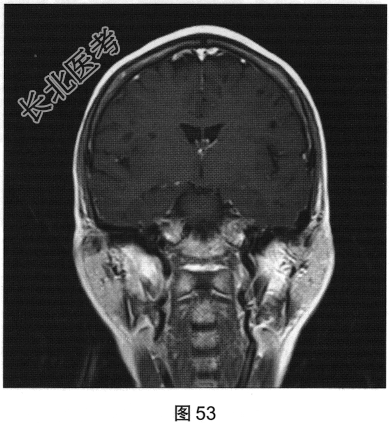

- 多项选择题2.[提示]患者行FLAIR、DWI及增强扫描,见图45~图54。该患者MRI影像的主要阳性表现有( )

C、双侧放射冠及半卵圆中心多发条状、圆形及卵圆形异常信号灶

E、病灶呈长T1、长T2信号,FLAIR为低信号,DWI为低信号,ADC为高信号

A、中脑处病变容易生长很大,可压迫第3脑室引起脑积水

B、病灶在所有MRI序列上均有脑脊液信号相似

C、是与穿动脉伴行的含有间质液体的由柔脑膜细胞包绕的囊性结构,与蛛网膜下腔相通